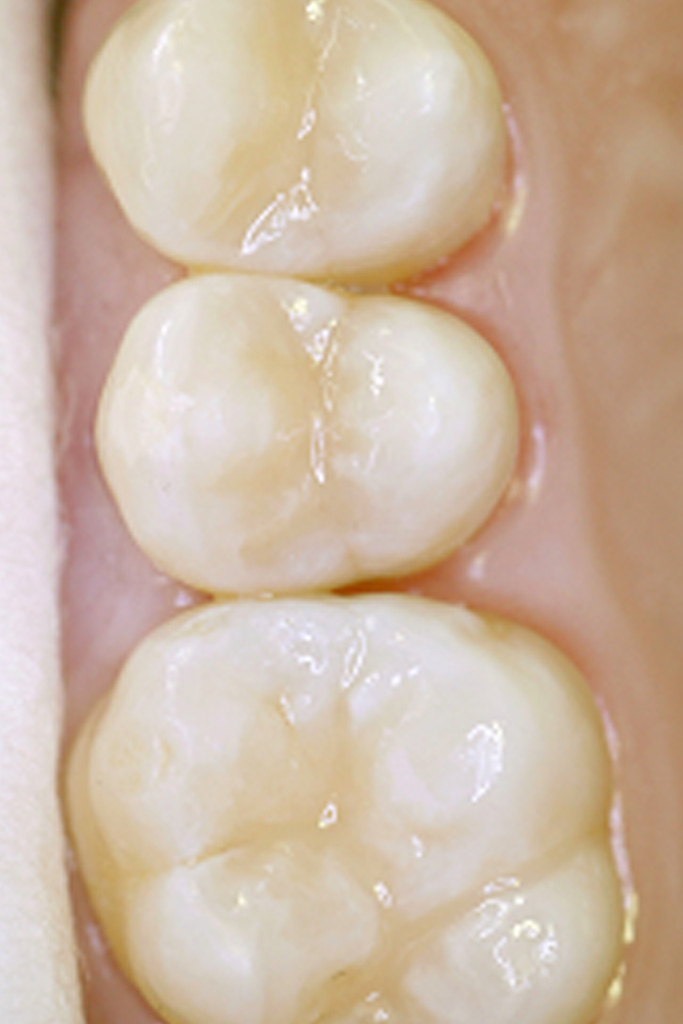

Die Fissurenversiegelung ist eine wichtige prophylaktische Maßnahmen zur Verhütung von Karies auf den Kauflächen der Milch- und bleibenden Backenzähnen (= Molaren + Prämolaren).

Durch die Versiegelung der meist haar- oder ampullenförmigen Spalten (=Fissuren) auf den Kauflächen wird das Eindringen von Mundhöhlenbakterien und Speiseresten verhindert. Da sich die Fissuren trotz intensiver Zahnpflege nicht reinigen lassen, muß vor jeder Versiegelung die in den Fissuren befindliche, kariesverursachende Plaque (= Nahrungsbestandteile + Bakterien) restlos beseitigt werden.

Nach konventioneller Methode wird zu diesem Zweck zunächst der Eingang der Fissur mit einem flammenförmigen rotierenden Instrument erweitert. Nur so ist eine Beurteilung des Spaltensystems und das Entdecken möglicher Kariesherde in der Fissur möglich. Nach Reinigung und Ausspülung der Fissur wird diese im Anschluß mittels eines am Zahnschmelz haftenden Kunststoffes verschlossen.

Zur Erhöhung der Sicherheit kann heute das bisherige Verfahren durch Einsatz des Lasers verbessert werden. Mit einer nur 0,32 mm dicken Glasfaser wird die Laserenergie in die Fissur geleitet. Ein zuvor in die Fissur eingebrachtes Initiatorgel erhöht dabei die Absorbtion der Lichtenergie auf der Oberfläche.